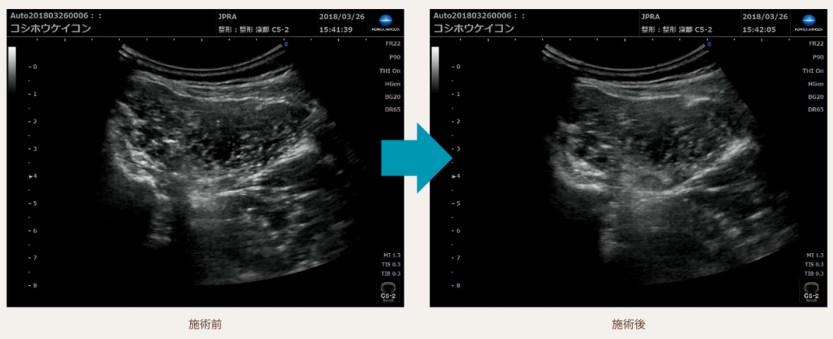

超音波エコーで証明された施術の変化

当院の施術による人体の変化を、超音波エコーを用いた科学的な方法で観察されました。

この進歩的な技術により、治療の効果が視覚的にも確認できるようになりました。

患者様は、この客観的な証拠に基づいた施術を受けることができます。

科学的な根拠に裏打ちされた当院のアプローチは、腰痛の改善に対して確かな信頼性を提供します。

科学的にも治療効果が認められています

「効率的に腰痛の改善を目指せる手技」

それを創り出すために、総額数億以上の研究費を費やし

手技の開発に没頭しました。

国立研究機関の協力のもと手技後の変化を可視化。

科学的にもその効果が立証されました。